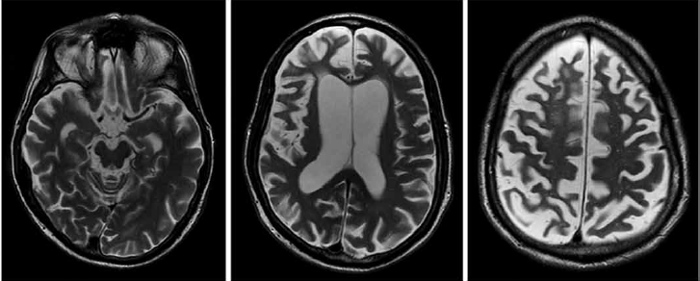

Observe a ressonância magnética a seguir.

(https://www.google.com/url?sa=i&url=https%3A%2F%2Fwww.pacificneuroscienceinstitute.org)

Um homem de 65 anos apresenta-se para avaliação neurológica com queixas de movimentos involuntários lentos e contorcidos afetando principalmente os membros superiores. Ele relata que esses sintomas começaram há cerca de dois anos e têm piorado progressivamente, interferindo nas atividades diárias, como escrever e manusear utensílios. O exame físico revela distonia axial leve e ausência de sinais parkinsonianos. Não há histórico familiar conhecido da condição. Com base na apresentação clínica e na imagem da ressonância desse paciente, qual dos seguintes diagnósticos é mais provável?